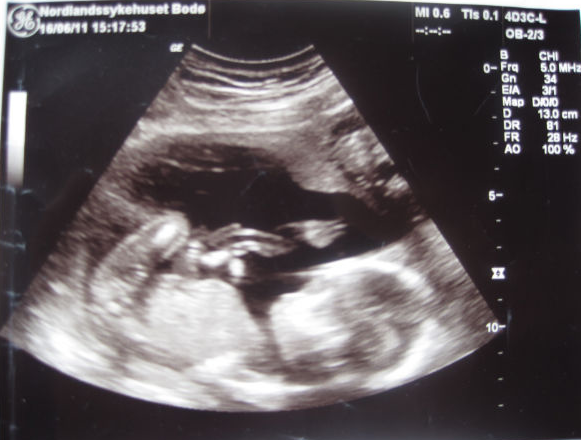

Teriyaki Skrevet 20. juni 2011 Forfatter #828 Skrevet 20. juni 2011 (endret) Jeg har hatt nesten flat mage begge svangerskap frem til uke 21-22, deretter har den poppet. Greit med nytt nick innimellom, har skiftet et par ganger jeg også Ja den kommer vel etter hvert! Snikleser melder seg. Nå vil jeg ha deg på mine innlegg. Gratulerer med gutt! hit! Alltid artig med sniklesere som melder seg Tusen takk for det! Har lagt inn bildene på pc nå, så tenkte jeg skulle legge ut de to beste. Endret 20. juni 2011 av Teriyaki

Gjest Delphina Skrevet 20. juni 2011 #829 Skrevet 20. juni 2011 Så skjønne bilder. Vi har tre av snuppa, to av dem i uke 13 og en av henne i uke 21. Alle sier hun smiler på uke 21 bildet, men tror hun bare svelget litt fostervann rundt den tiden.

Gjest Krizzy Skrevet 20. juni 2011 #832 Skrevet 20. juni 2011 hit! Alltid artig med sniklesere som melder seg Tusen takk for det! Har lagt inn bildene på pc nå, så tenkte jeg skulle legge ut de to beste. Ja, nå orka jeg ikke drive å finne fram lengre. Mye enklere å ha deg på mine innlegg.... Så nydelig liten gutt!